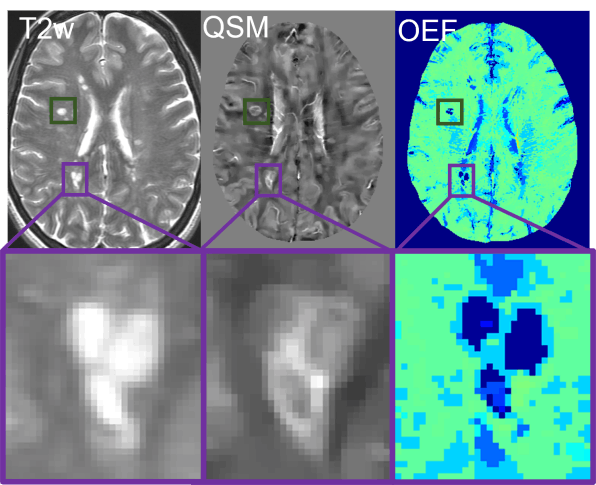

Clinical Application

To investigate disease progression and therapeutic strategies, we are applying our technique into neurologic disorders.

See our recent work in stroke, multiple sclerosis, dementia, brain cancer, pre-eclampsia